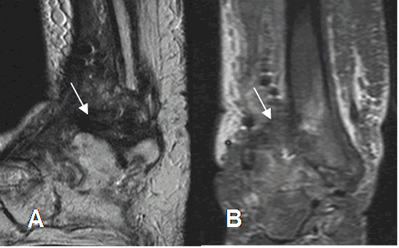

Fig 132. Artropatía neuropática en fase crónica.

A: RM sagital en T2 y B: RM coronal en STIR. Cambios residuales con signos de sinovitis crónica, hipointensa en ambas secuencias.